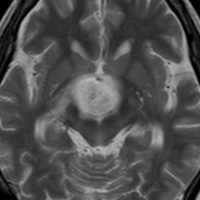

7歳の子が視力障害で発症しました。両耳側半盲という症状です。典型的な鞍隔膜下頭蓋咽頭腫です。ガドリニウム造影剤を入れないMRIでみえる,黄色い矢印の先の白い高信号は抗利尿ホルモンです。ですから下垂体機能もまだ残っていて,尿崩症はありません。視力障害が戻らないことがあるのでなるべく早く,経鼻的な手術で摘出した方がいいものです,簡単 o(^-^)o